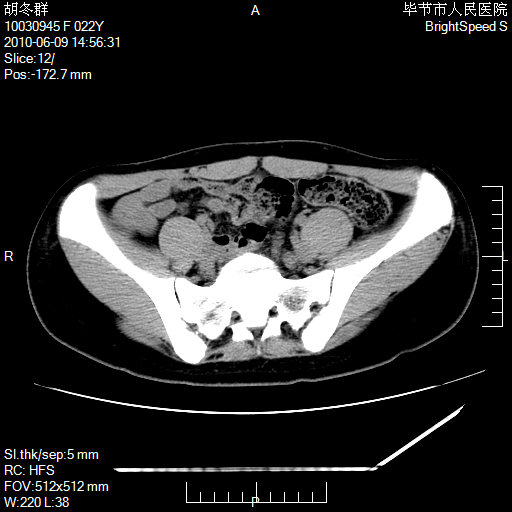

患者23岁,发现腹部包块3月。

盆腔内囊性占位;穿刺或者直接手术拿掉即可,不必紧张。

左侧卵巢囊腺瘤或囊腺癌

盆腔内囊性占位性病变;考虑左侧卵巢囊腺瘤。

有分隔、壁薄,支持考虑左侧卵巢囊腺瘤。

左侧卵巢浆液性囊腺瘤。

支持左侧附件区囊性占位,多考虑为囊腺瘤。

支持考虑左侧卵巢囊腺瘤;宫腔积液。

有分隔、壁薄,支持考虑左侧卵巢囊腺瘤。排尿后,膀胱缩小,由于重力作用,肿块下移就到了膀胱位置,很好理解。